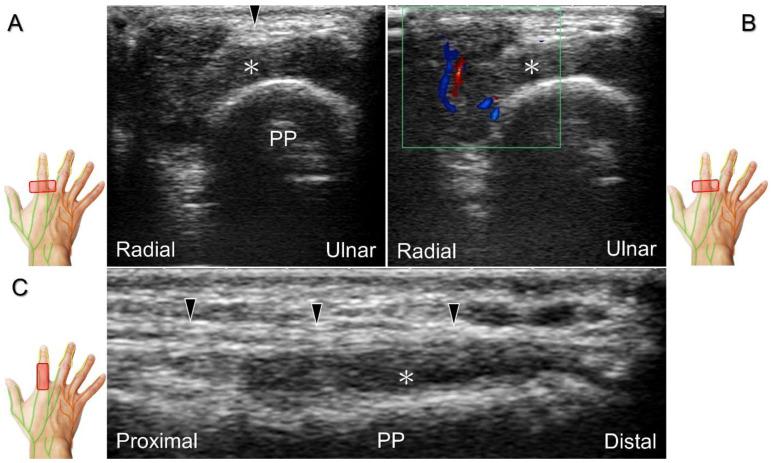

超声已成为一种极具价值的工具,用于腕部区域周围神经病变的成像,特别是对于诸如腕管综合征和尺神经管综合征等常见病症。大量研究表明,神经在卡压部位近端肿胀、边界不清和平扁是神经卡压的特征。然而,关于腕部和手部的小神经或终末神经的信息却很匮乏。本文旨在通过全面概述这些神经卡压的扫描技术、病理学和引导注射方法来填补这一知识空白。本综述详细阐述了正中神经(主干、掌皮支和返支)、尺神经(主干、浅支、深支、掌尺皮支和背尺皮支)、桡浅神经、骨间后神经、掌总/指固有神经和背总/指固有神经。一系列超声图像用于详细说明这些技术。最后,超声检查结果补充了电诊断研究,有助于更好地理解整个临床情况,而超声引导下的干预措施对于治疗相关神经病变是安全有效的。